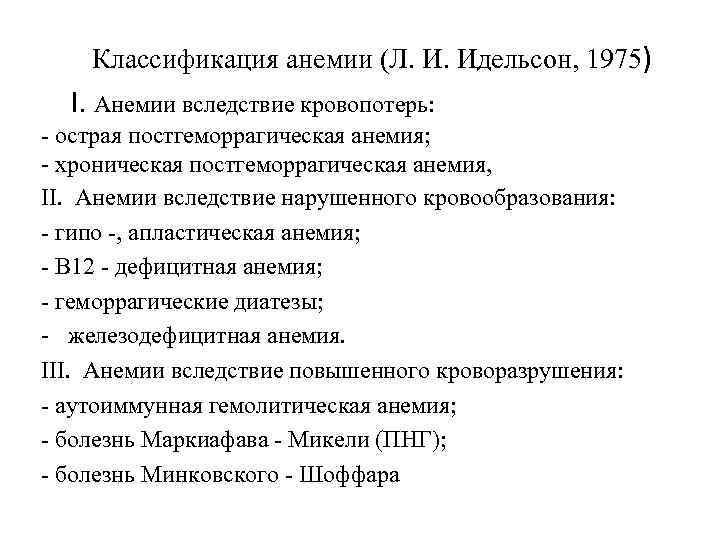

Классификация анемии (Л. И. Идельсон, 1975) I. Анемии вследствие кровопотерь: - острая постгеморрагическая анемия; - хроническая постгеморрагическая анемия, II. Анемии вследствие нарушенного кровообразования: - гипо -, апластическая анемия; - В 12 - дефицитная анемия; - геморрагические диатезы; - железодефицитная анемия. III. Анемии вследствие повышенного кроворазрушения: - аутоиммунная гемолитическая анемия; - болезнь Маркиафава - Микели (ПНГ); - болезнь Минковского - Шоффара